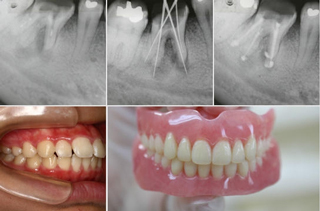

歯の根の治療は、大きく化膿した場合でも根気よく治療すれば抜歯せず残せる可能性があります。歯の根の治療や歯周病、入れ歯の治療は院長の担当となります。